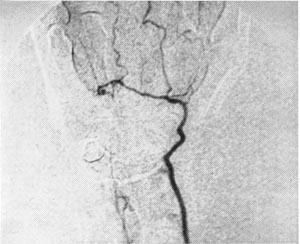

The device was sold as the DSP 9300. Figure 3 shows a non-invasive angiogram study using the DSP 9300.